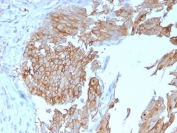

UPK1B Antibody for IHC. Immunohistochemistry analysis of Uroplakin 1B / UPK1B antibody in human urothelial carcinoma tissue using clone UPK1B/3102. FFPE sections show strong HRP-DAB brown membranous staining in tumor epithelial cells, highlighting the organized apical membrane pattern consistent with urothelial plaque structures. This Urothelial Plaque Structural Protein Antibody emphasizes the role of UPK1B in plaque assembly and membrane ultrastructure within urothelial tumor cells. HIER: boil tissue sections in pH 9 10mM Tris with 1mM EDTA for 20 minutes followed by cooling prior to staining.

UPK1B expression is largely restricted to urothelial tissues including bladder, ureter, and renal pelvis, with localization concentrated at the apical membrane of superficial umbrella cells where plaque structures are most abundant. Staining is typically observed as strong membranous labeling corresponding to dense uroplakin plaque regions. Clone UPK1B/3102 antibody provides consistent recognition of UPK1B, and the UPK1B/3102 monoclonal antibody format supports reproducible detection of this urothelial plaque structural protein in studies focused on membrane architecture and epithelial ultrastructure.